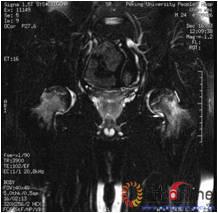

病灶修复情况比较,加用BMP2组病灶修复的完全性及硬化骨数量普遍优于未加BMP2组。(图3)

图3-1 女,31岁,SARS患者骨坏死,(1)MRI示双侧股骨头坏死,右Ⅱb(B型),左Ⅱc(C1型);(2)打压植骨术(未加BMP2)后坏死修复不完全,仍遗留股骨头软骨下病灶未完全修复, 5年随访关节功能优(Harris评分96分)

图3-2 女,30岁,SARS患者骨坏死,(1)术前MRI示双侧骨坏死;右Ⅱc期C3型,左Ⅱb期B型,打压植骨术(加BMP2),(2)5年后CT显示病灶修复好,关节功能优